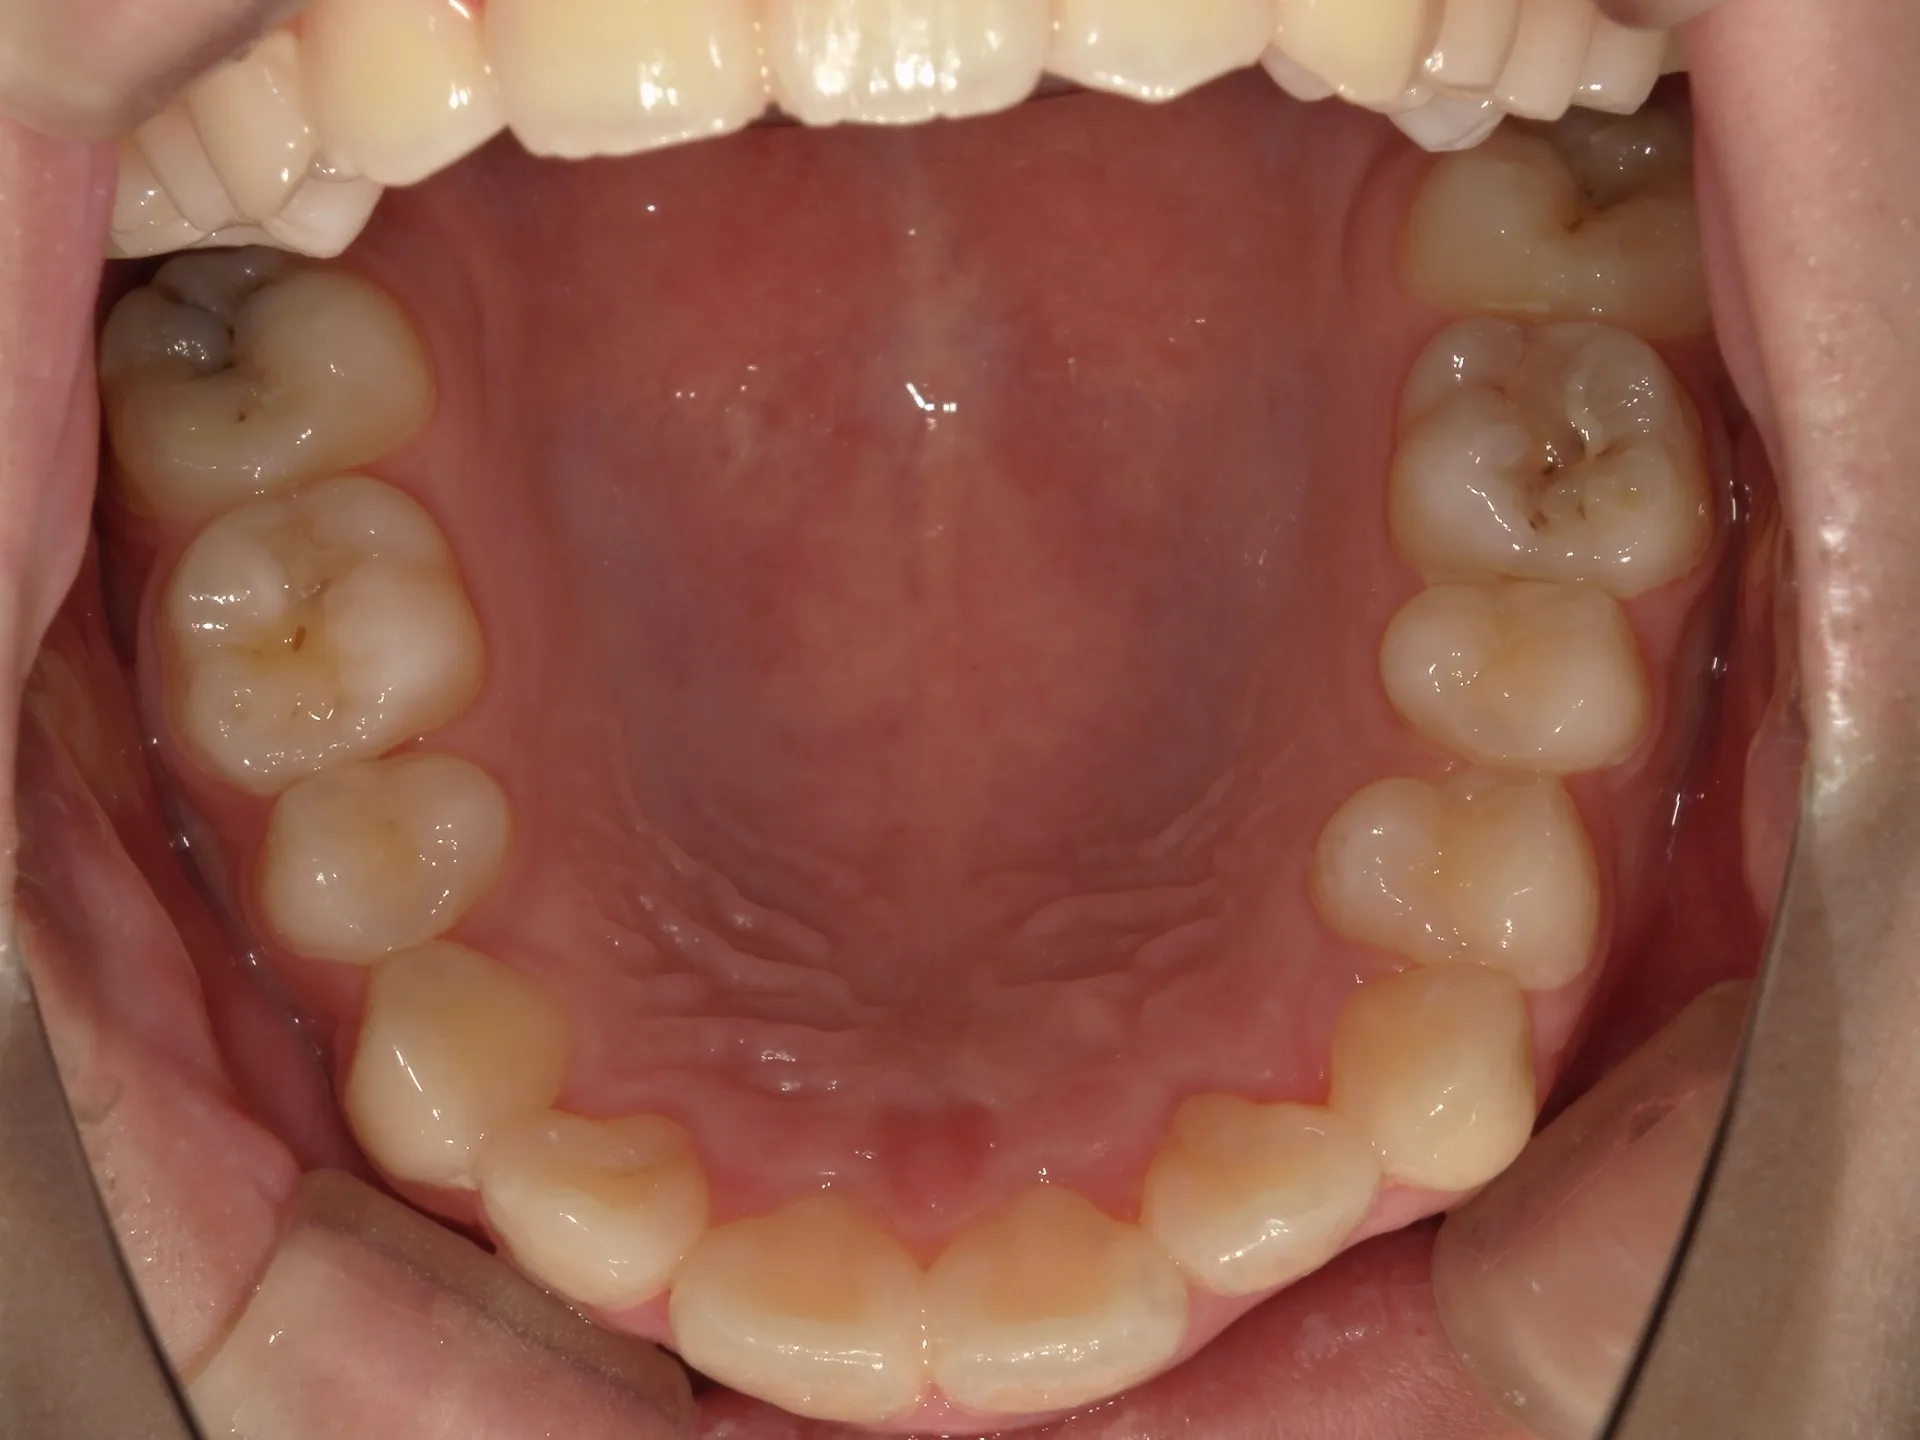

今回は下の前歯が1本ない場合の矯正治療についてご紹介いたします。